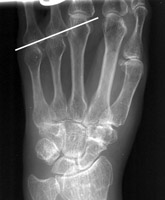

Metacarpal Sign

Short 4th Metacarpal

Radiograph of the hand which reveals an abnormally short 4th metacarpal, as compared to the other metacarpal bones. Although this sign usually is associated with Turner's syndrome, the short 4th "metacarpal sign" carries a short differential diagnosis and is therefore not pathognomonic.